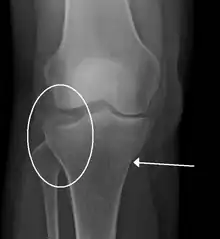

A tibial plateau fracture

- Tibial plateau fracture

- Bumper fracture - a fracture of the lateral tibial plateau caused by a forced valgus applied to the knee

- Segond fracture - an avulsion fracture of the lateral tibial condyle